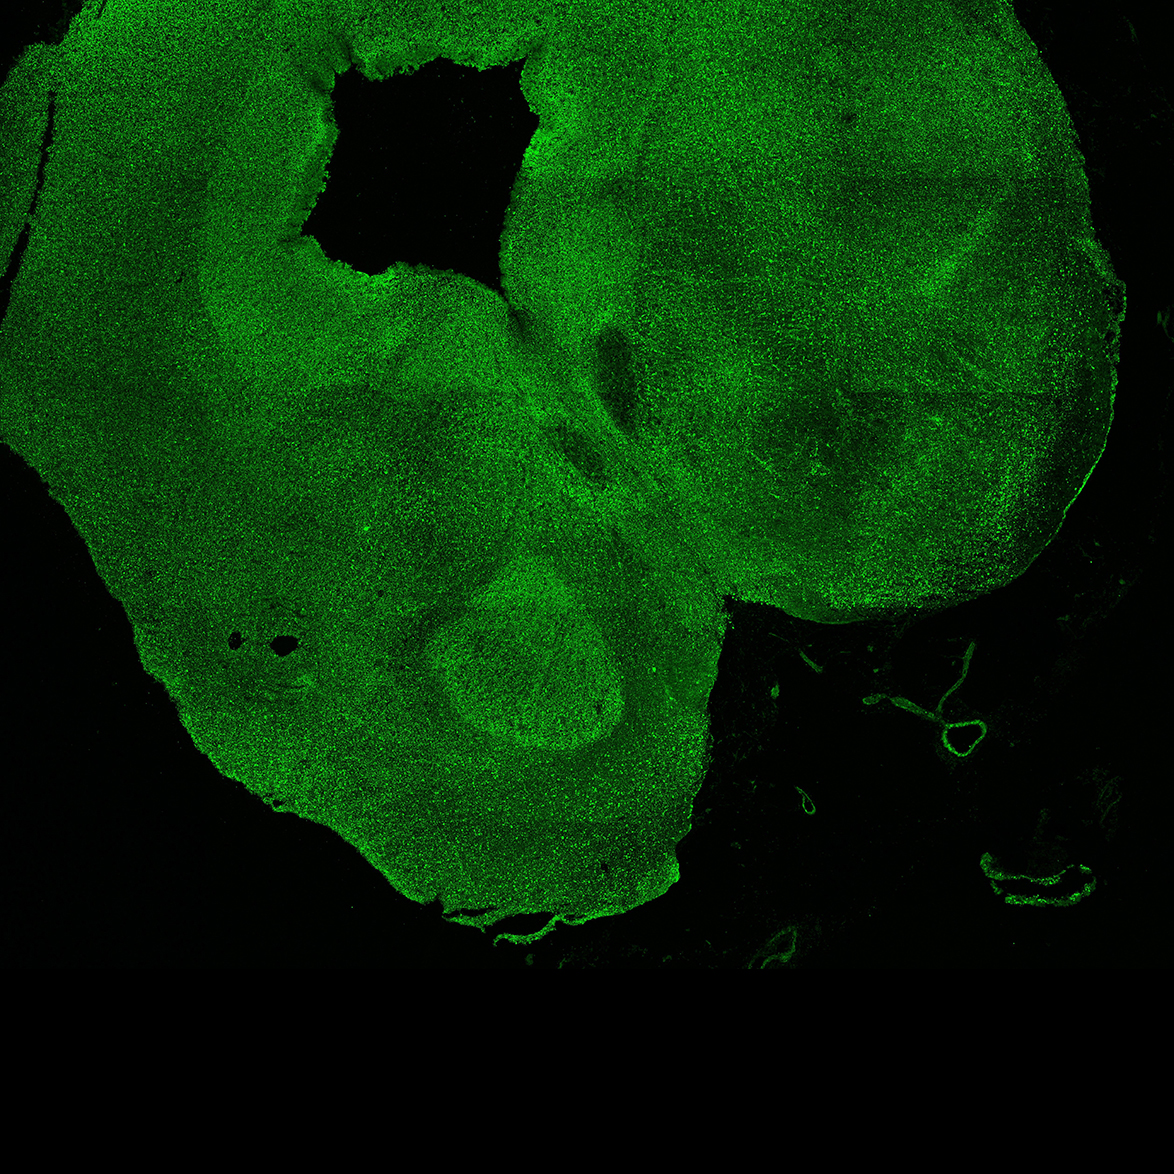

An anatomical analysis of the developing human midbrain from 6 post-conceptional weeks (PCW) to 22 PCW reveals increased tissue complexity, characterized by the emergence of dopaminergic nuclei, as highlighted by immunofluorescence analysis for tyrosine hydroxylase (TH).

11PCW

DAPI

11PCW human midbrain

MAP2

SOX2

Merged